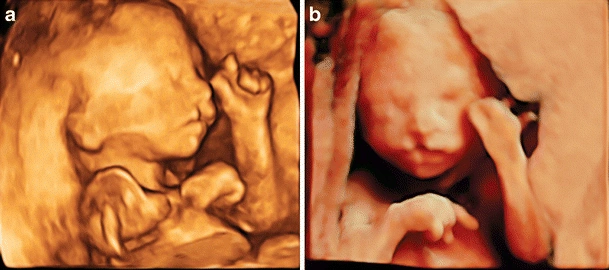

Siêu âm 4D (4 chiều) là một kỹ thuật chẩn đoán hình ảnh tiên tiến, cho phép chúng ta quan sát thai nhi dưới dạng một video chuyển động theo thời gian thực. Thay vì những hình ảnh 2D phẳng hay 3D tĩnh, công nghệ 4D mang đến những thước phim sống động, giúp cha mẹ thấy rõ từng cử chỉ, biểu cảm của bé như ngáp, mút tay, hay nhăn mặt.

Giá trị lớn nhất của hình ảnh siêu âm 4D thai 24 tuần không chỉ nằm ở cảm xúc gắn kết mà còn giúp bác sĩ đánh giá chính xác hơn chức năng vận động và sàng lọc dị tật một cách hiệu quả.